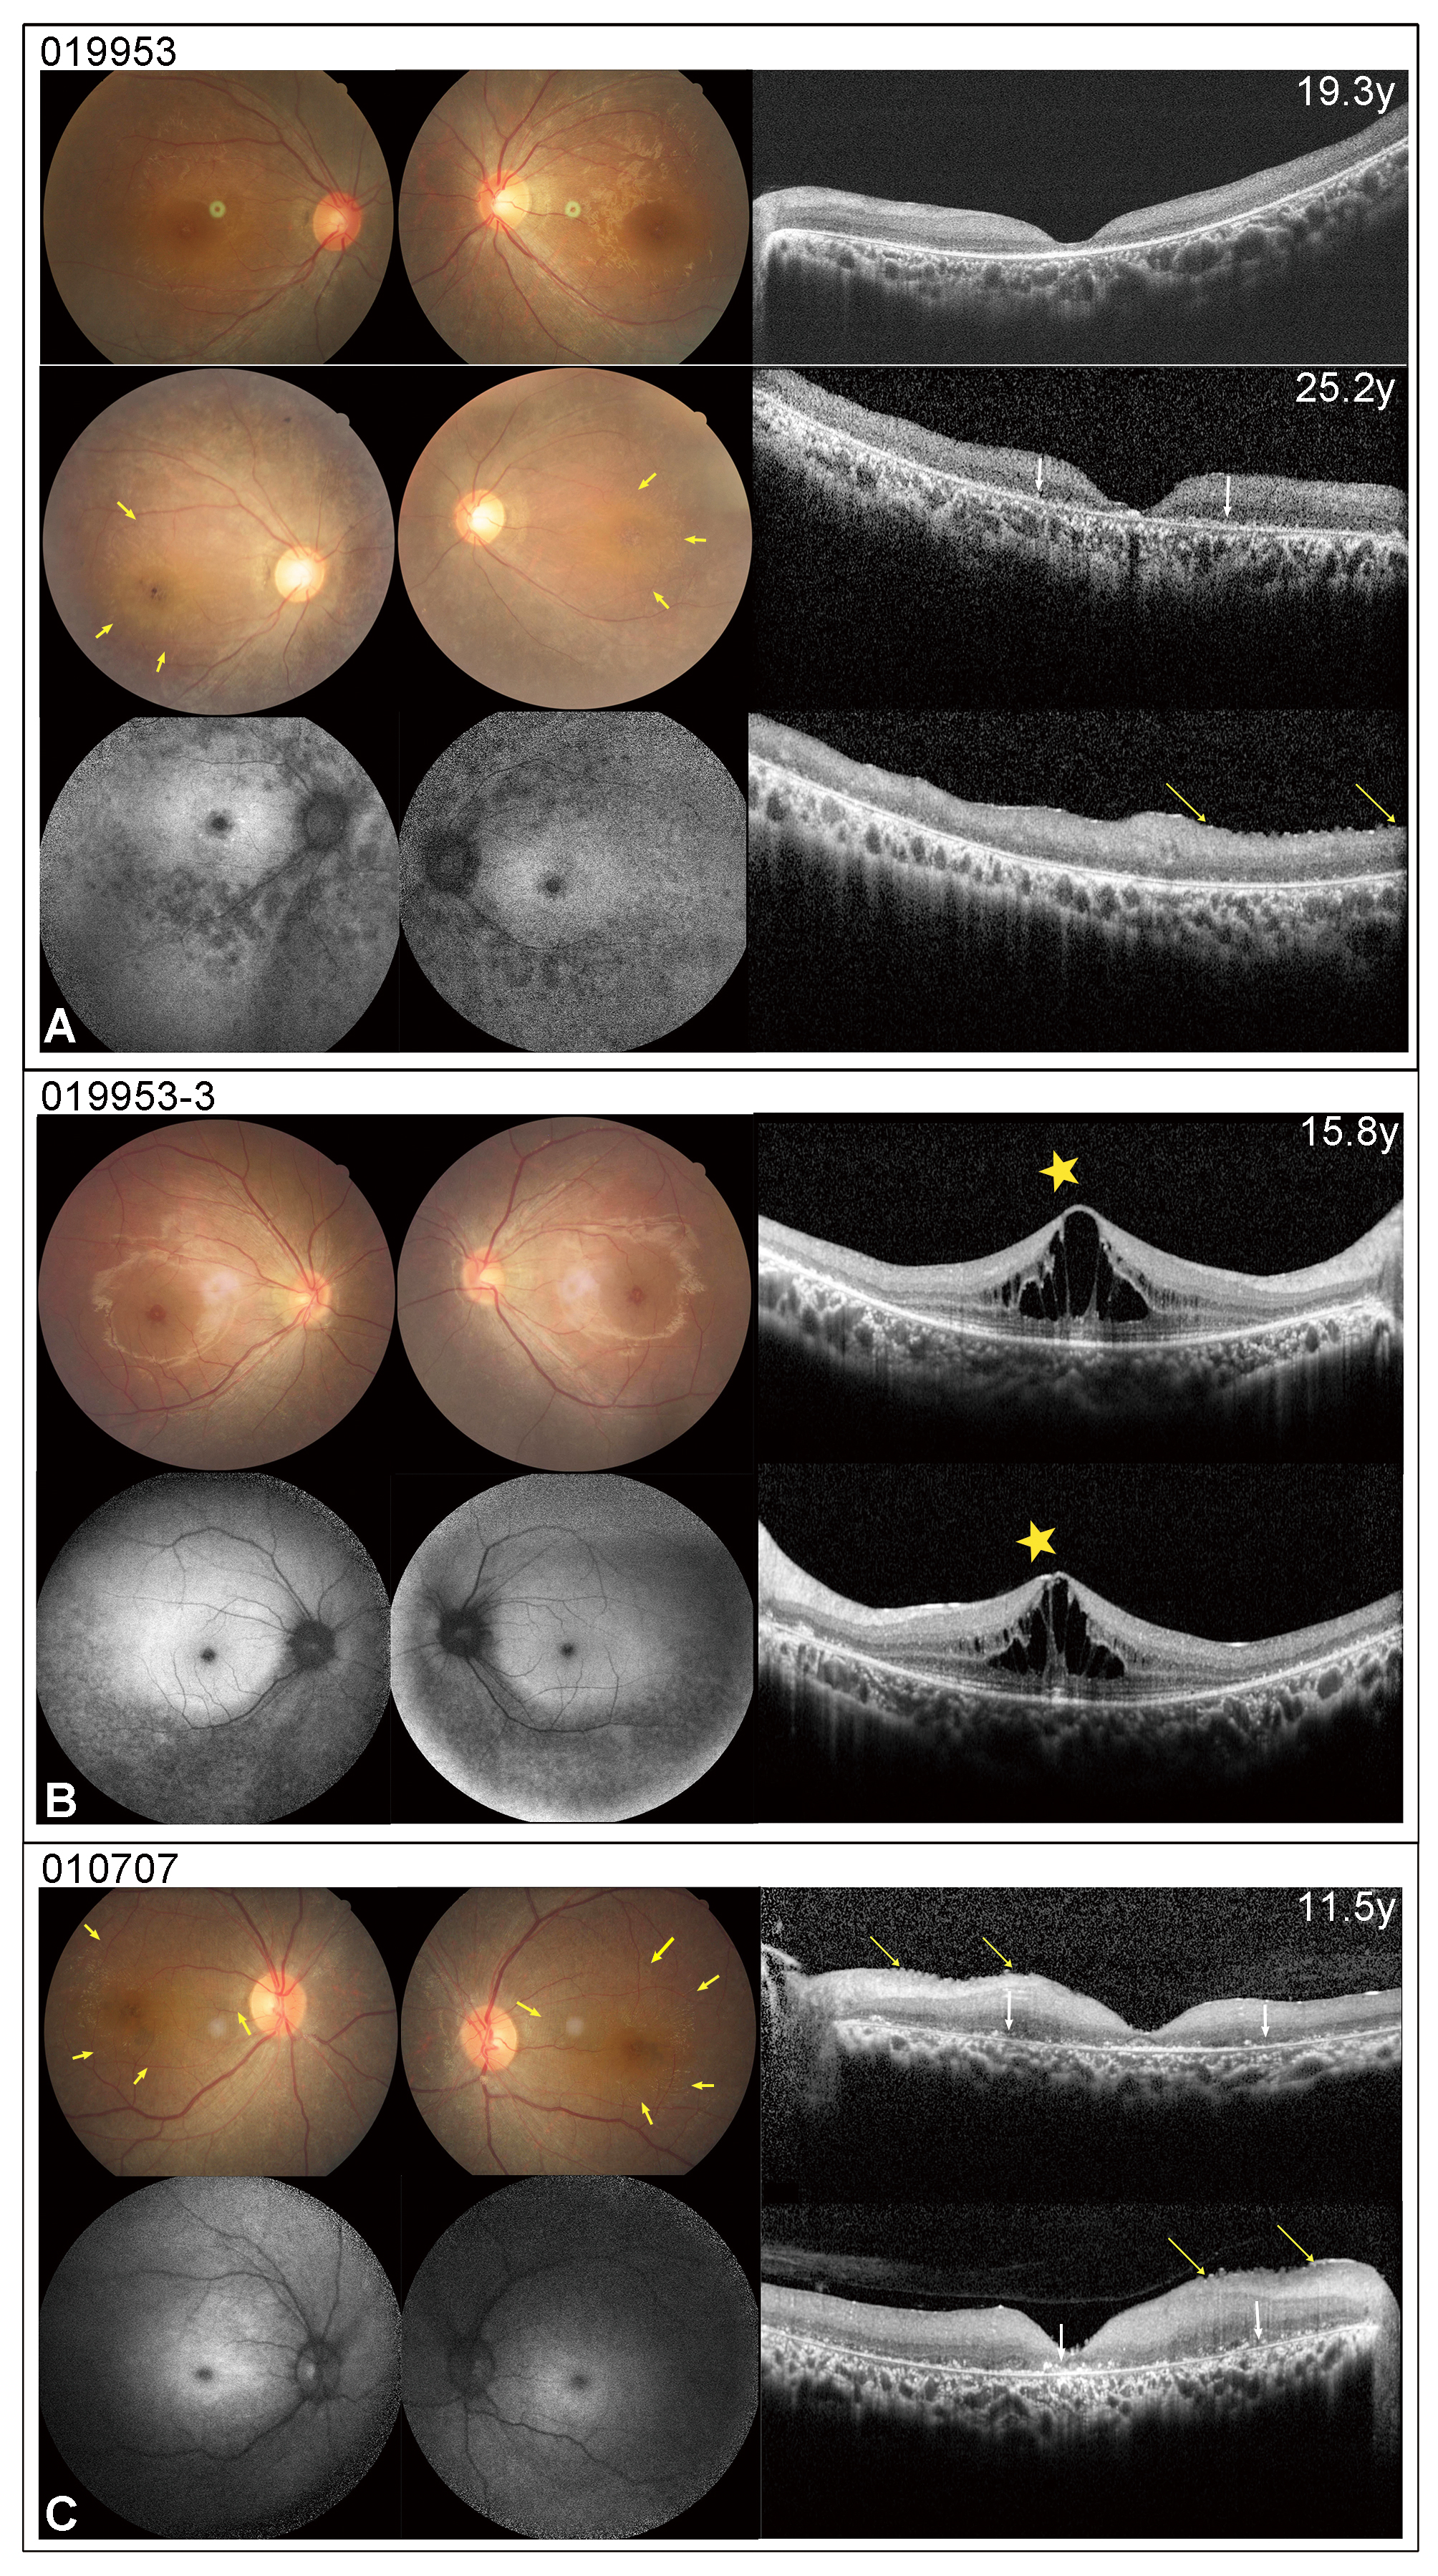

Figure 4. CF photographs, FAF, and OCT images of three patients carrying PPT1 variants. A CF image of patient 019,953 showed a blunted foveal reflex and mild retinal degeneration (RD) in the peripheral retina, while

her OCT scan displayed macular atrophy at the age of 19.3 years. Her CF and OCT images indicated macular striation (yellow

arrows), a total loss of ellipsoid zone, and hyper-reflective dots in the RPE level (white arrow) at the age of 25.2 years.

Her FAF displayed an enlarged area of hypo- AF area in the foveal region, surrounded by a hyper-AF region in the posterior

pole and a patchy hypo-AF region in the midperipheral retina. B CF and OCT of patient 019,953-3 showed marked macular edema (yellow asterisk) and peripheral RD. His FAF appearance was similar

to that of his sister (patient 019,953). C CF, OCT, and FAF images of patient 010,707 disclosed a fundus appearance akin to that observed in patient 019,953 at the

age of 25.2 years.